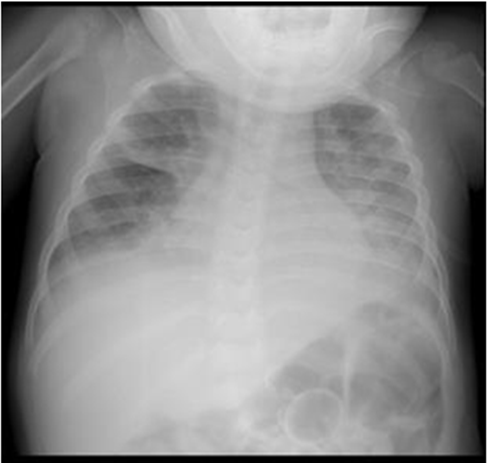

Upon admission to the emergency room, chest X-ray (X-ray) revealed veiling at the apex of the right lung and opacity in the perihilar region of both hemithorax (Figure 1A), with RT-PCR for SARS-CoV-2 being collected, with a negative result.

The patient was kept on NIV using the Bennett 840® device, with a non-ventilated full face mask, interspersed every six hours by an orofacial mask for six consecutive days. The ventilatory parameters used, as well as the SpO2 / FiO2 and PaO2 / FiO2 ratio can be seen in Table 1, as well as the chest x-ray (Figure 1B) showing improvement of the image compared to Figure 1A of the admission.